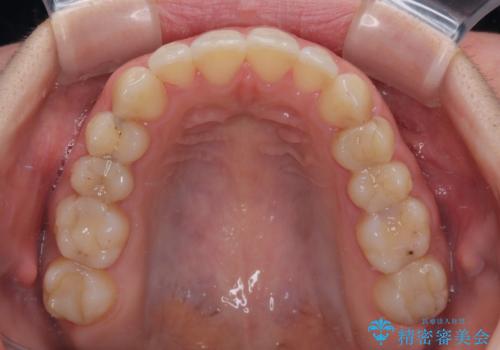

【モニター】オープンバイトをインビザライン矯正で治す

- 前歯の開咬を気にして来院された患者様です。

開咬の治療は、前歯を閉じるように動かすとともに、上下臼歯を圧下(骨内にめり込ませる)させることで進めて行きます。

インビザラインは臼歯の圧下を効果的に行えるため、インビザラインを用いて矯正治療を行うこととしました。